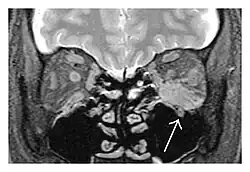

Right optic disc lesion in IgG4-ROD

Mass lesion around the right optic disc in a 44-year-old man with IgG4-related ophthalmic disease and a serum IgG4 of 599 mg/dL.[1] (T2-weighted MRI)

The extent of inflammation that can occur in IgG4-ROD is well demonstrated on magnetic resonance imaging (MRI).